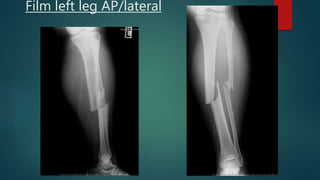

 Film left leg AP/lateral

Film left leg AP/lateral

Investigation  Film CXR– normal  Film skull AP/lateral – no fracture  Film pelvic AP – no fracture  Film left leg AP/lateral

Film left legAP/lateral